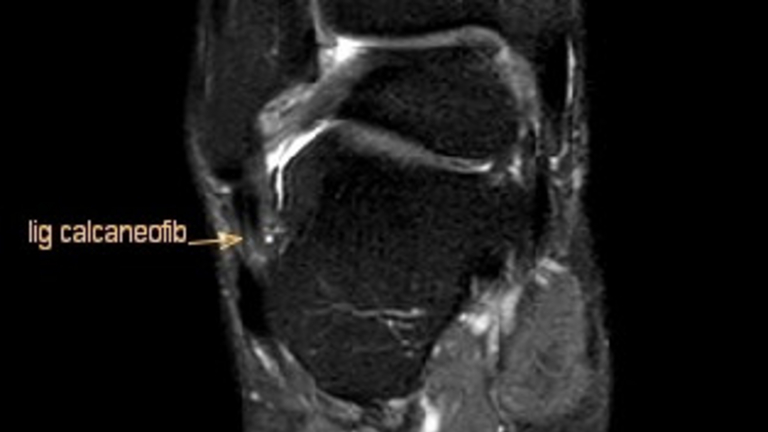

Die Diagnose beginnt mit einer körperlichen Untersuchung. Dabei prüft der Arzt Schwellung, Druckschmerz und Bandstabilität. Um Brüche auszuschließen, wird oft ein Röntgenbild angefertigt. In unklaren Fällen oder bei Verdacht auf Bänderriss kann zusätzlich eine Ultraschall- oder MRT-Untersuchung erfolgen.